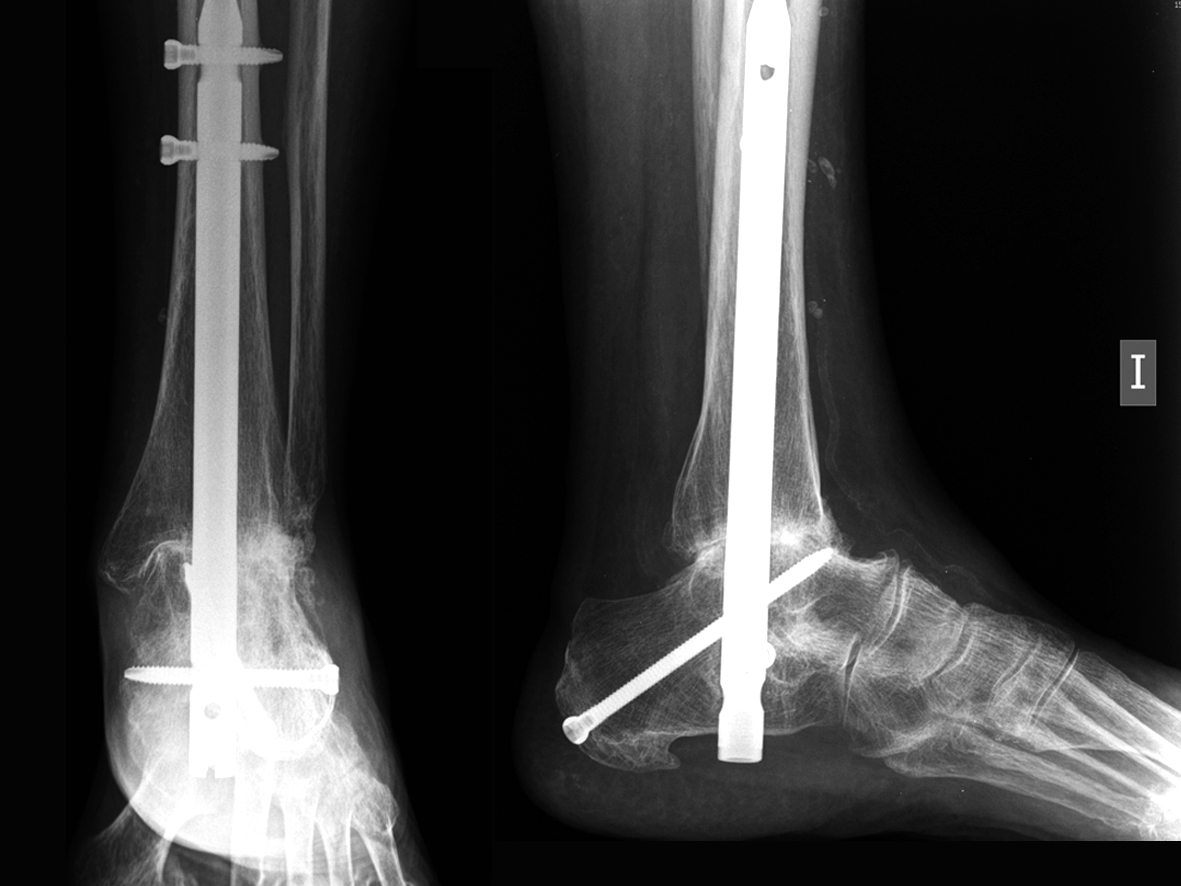

10. Tibiotalar Arthritis

Ankle fractures, infection, osteonecrosis, and arthritis may eventually lead to chronic pain and stiffness that can not be controlled with nonoperative measures. Ankle fusion is a treatment option appropriate for many patients in this situation. When performed by an experienced surgeon, ankle arthroscopy offers a minimally invasive way to perform ankle fusion that may yield results that are equal to or better than conventional open techniques. This procedure has its limitations. Your surgeon can determine if this procedure is an appropriate option for you.